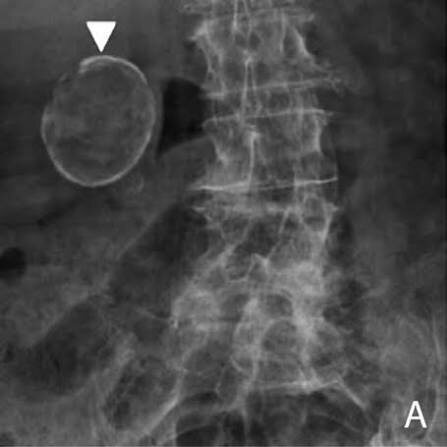

«Фарфоровый» желчный пузырь

Бывают случаи, когда стенки желчного пузыря кальцинируются, вследствие длительных воспалительных процессов в желчном или из-за нарушения желчеоттока происходит нарушение обмена веществ, повышается концентрация солей кальция. В любом случае, при выявлении признаков «фарфорового» желчного пузыря, необходимо проведение холецистэктомии, так как есть риски возникновения озлокачествления процесса. Можно диагностировать с помощью рентгенографии ОБП, узи, МРТ. Возможно появление болей в правом подреберье, горечи во рту, дискомфорта.